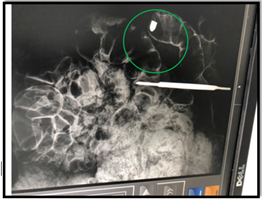

As an example of the importance of the X-Ray apparatus in the Necropsy exam, we present a clinical case, researched and drafted by the forensic expert Claude Jacques Chambriard, in which the projectile was lodged inside a segment of the Colon, the location of its position only being possible with the aid of the X- Ray device.

In the photograph to the right, taken at the Regional Technical-Scientific Police Precinct (PRPTC) in Niterói, we demonstrate the use of the X-Ray machine during the search for a projectile in the corpse, which is subsequently identified inside the large intestine.

The presence of the scalpel in the image is due to the fact that it is used as a scale of reference for  the location of the projectile.